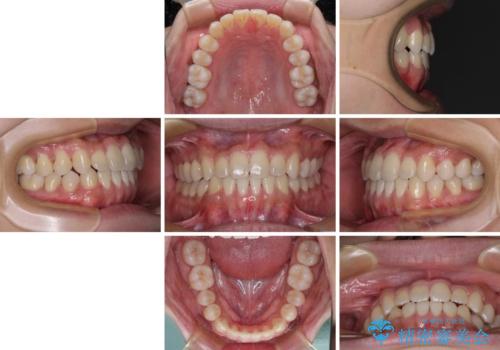

骨格的な左右差も顕著であったため、正中は合わず、上下前歯の一部が接触しない咬み合わせとなることが予想されましたが、正中はもともとのズレが小さかったことから、合わせることができました。

治療期間も10か月間という短期間で終了し、患者様には大変満足していただきました。